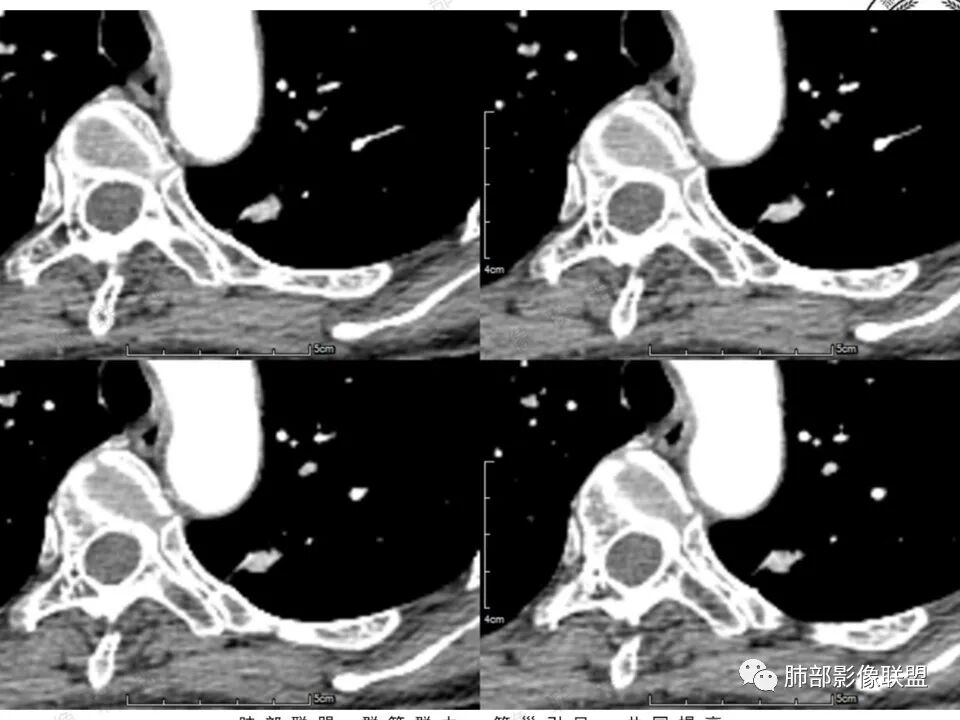

1.中年女性,体检发现;2.左肺上叶后段长条形结节灶,边缘有膨隆,也有收缩,腺癌和炎性结节都可以,但是周围见边界清楚磨玻璃影强烈提示腺癌可能性。3.显著强化的肺结节,无论如何都应当引起我们的高度重视!尽管炎性病灶和新生物都可以,尽管强化程度不能作为诊断癌肿的依据。

4.本例结节强化程度明显低于主动脉,也缺乏血管畸形的典型的迂曲结构,血管畸形可能性不大。

★存在边界清楚的磨玻璃影,常常提示腺癌的可能性,尤其随诊复查没有变化。